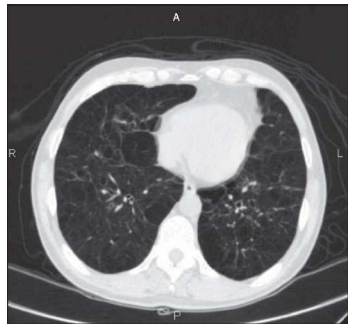

Orgão: IAMSPE

Um homem de 66 anos de idade, tabagista (carga tabágica de 150 maços/ano), portador de insuficiência cardíaca, diabetes e hipotireoidismo, procurou ajuda, no hospital local, por tosse, com expectoração amarelada, e piora da dispneia basal há dois dias. Nega febre. Ao exame, encontrava-se emagrecido e hidratado, com ACV: RCR em dois tempos, bulhas normofonéticas, FC de 80 bpm, MV+ bilateralmente, com sibilos esparsos e roncos, FR de 30 irpm e membros inferiores sem edemas. Laboratório: Hb 15.8; leucócitos 9.000, sem desvios; PCR 5 (ref. 0,5); Cr 1.5; UR 60; glicose 146; Na+ 146; e K+ 4.6. Gasometria: pH 7.3; PaCO2 60; HCO3 30.2; BE+ 7; e sat. de O2 de 87% em ar ambiente. Realizou a tomografia de tórax mostrada a seguir.

Enunciado 1994018-1

Internet: Pulmão RJ 2013;22(2):45-49.

Com base nessa situação hipotética, assinale a alternativa que apresenta, correta e respectivamente, o diagnóstico mais provável e a conduta a ser adotada.